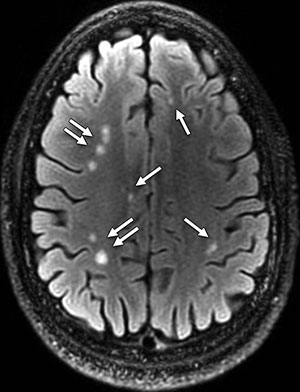

The MRI scans revealed the presence of white matter T2 hyperintensities, which can be thought of as brain scars, in 52 percent of the MTBI patients.

"We were really surprised to see so much damage to the brain in the MTBI patients," Dr. Riedy said. "It's expected that people with MTBI should have normal MRI results, yet more than 50 percent had these abnormalities."